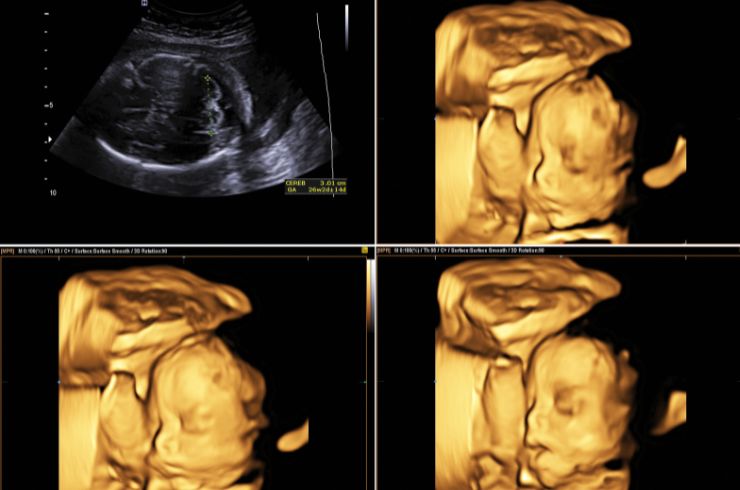

Equipped with advanced ultrasound machines, we ensure high-resolution imaging for precise, fast, and safe diagnostic evaluations by expert radiologists.

Adding further strength to the hospital’s reputation is Dr. Aarifa Aadil, a gold medalist gynecologist and radiologist trained at KGMU Lucknow. With over 14 years of experience, including work with Indira IVF Delhi, she provides high-quality ultrasound diagnostics using advanced 3D/4D imaging, as well as complete obstetric and gynecological care—from antenatal checkups